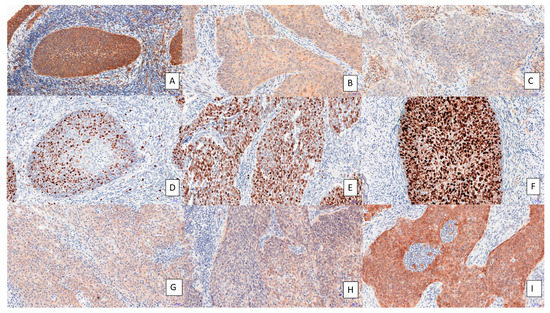

3.1. IHC on Tissue Samples